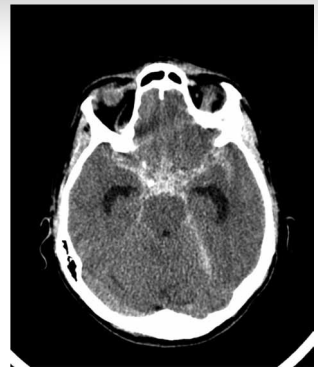

Assinale a alternativa correta em relação a imagem a seguir:

Corresponde à hemorragia subaracnoidea de provável etiologia aneurismática.

Corresponde à hemorragia subaracnoidea de provável etiologia traumática.

Corresponde ao sinal do cerebelo branco relacionado a edema cerebral difuso.